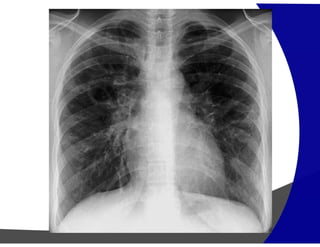

Fibrose Pulmonar

Achados por Imagem

• Raio – X – geralmente normal

Avançada – redução volumétrica e opacidade reticulares

subpleurais com gradiente de apresentação ápico-basais.

• TCAR

Redução volumétrica

Opacidades reticulares subpleurais

Faveolamento (macro)

Bronquiectasias de tração

Gradiente de envolvimento apico-basal

Heterogenicidade espacial e temporal de distribuição